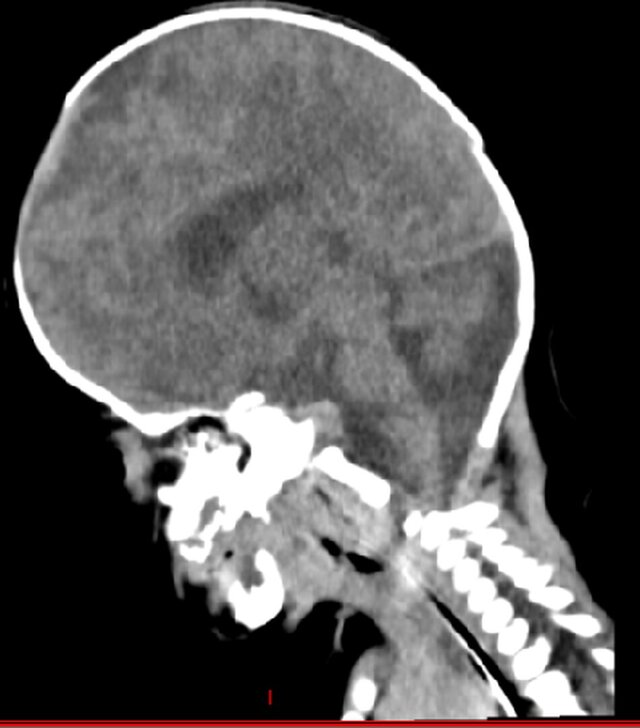

# Advanced 3D Modeling and Printing for Neonatal Apert Syndrome I led and supervised a dedicated team in reconstructing a highly precise neonatal cranium model for a patient affected by Apert syndrome, leveraging advanced HRCT data and parametric modeling techniques. Through meticulous analysis and collaborative innovation, we converted complex imaging data into a detailed 3D model that accurately represented the unique cranial anatomy of the patient. The model was then expertly 3D printed, serving as a critical surgical aid to enhance preoperative planning and precision during the procedure. This achievement underscores the transformative potential of integrating medical imaging with cutting-edge modeling and printing technologies to address complex craniofacial conditions, setting a benchmark for future interdisciplinary collaborations. For example, the detailed 3D representation allowed surgeons to simulate surgical approaches, reducing risks and ensuring better outcomes for the patient.